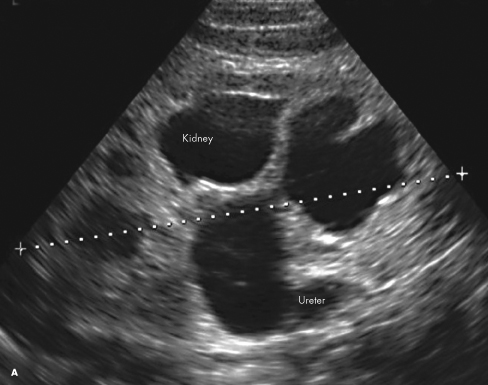

ectopic ureterocele

Saleem Raza, MD; Deepak M. Kamat, MD, PhD; Rajan Arora, MD; Rozanandham Samudrala, MD